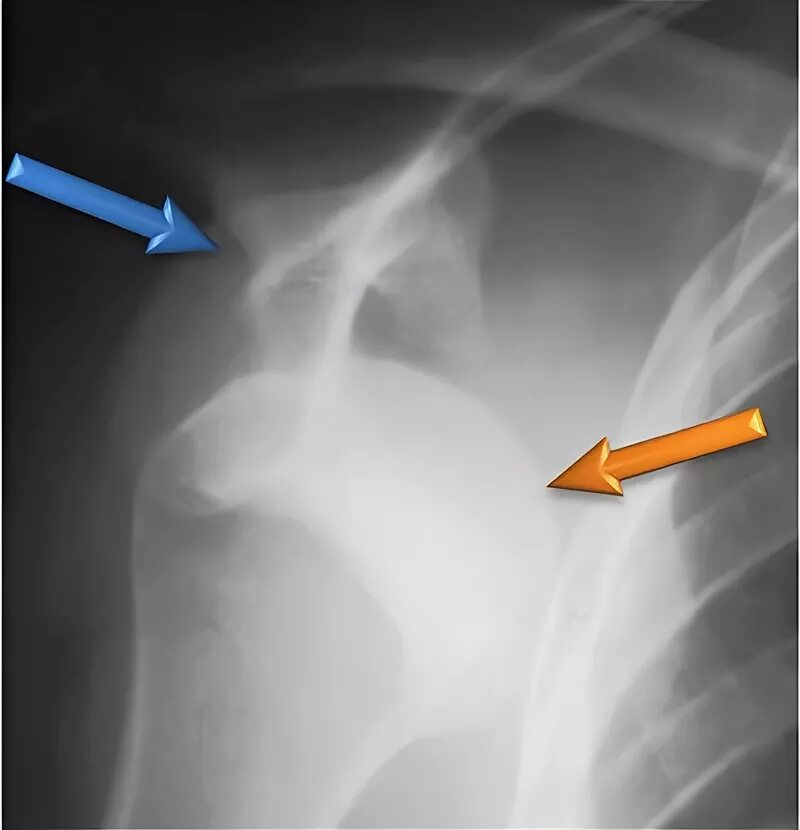

Нестабильность плечевого сустава мкб